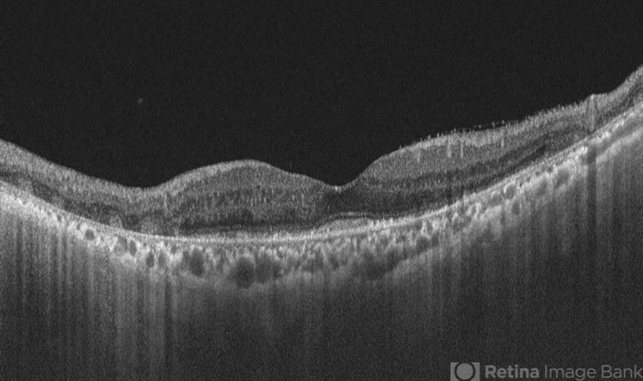

- OCT image of left eye of a 72 yr male with history of progressive loss of vision and loos of field of vision more in left eye. The OCT shows a trizonal pattern of outer retinal loss.